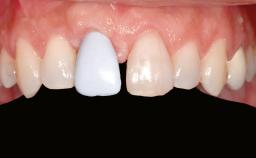

A 46-year-old woman was referred for treatment whose main complaints were mobility of her fixed partial dentures (right maxilla and left mandible) and periodontal bleeding during function. She also reported having taken systemic antibiotics to treat recurrent swelling in the area of the upper left molars. The patient had not seen a dentist for at least 2 years. She did not smoke and had no history of major systemic disease other than two minor orthopedic procedures some years back. The first-visit examination revealed poor plaque control, tooth mobility, periodontal disease, and a residual dentition widely associated with deep periodontal pockets.

| Patient's Esthetic Expectations | Low | Medium | High |

| Lip Line | No exposure of papillae | Exposure of papillae | Full exposure of mucosa margin |